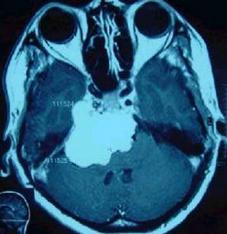

比如这一副图,我们从磁共振上可以看到有一块巨大的肿瘤(白色高亮区域),这就是肿瘤引起的面肌痉挛。